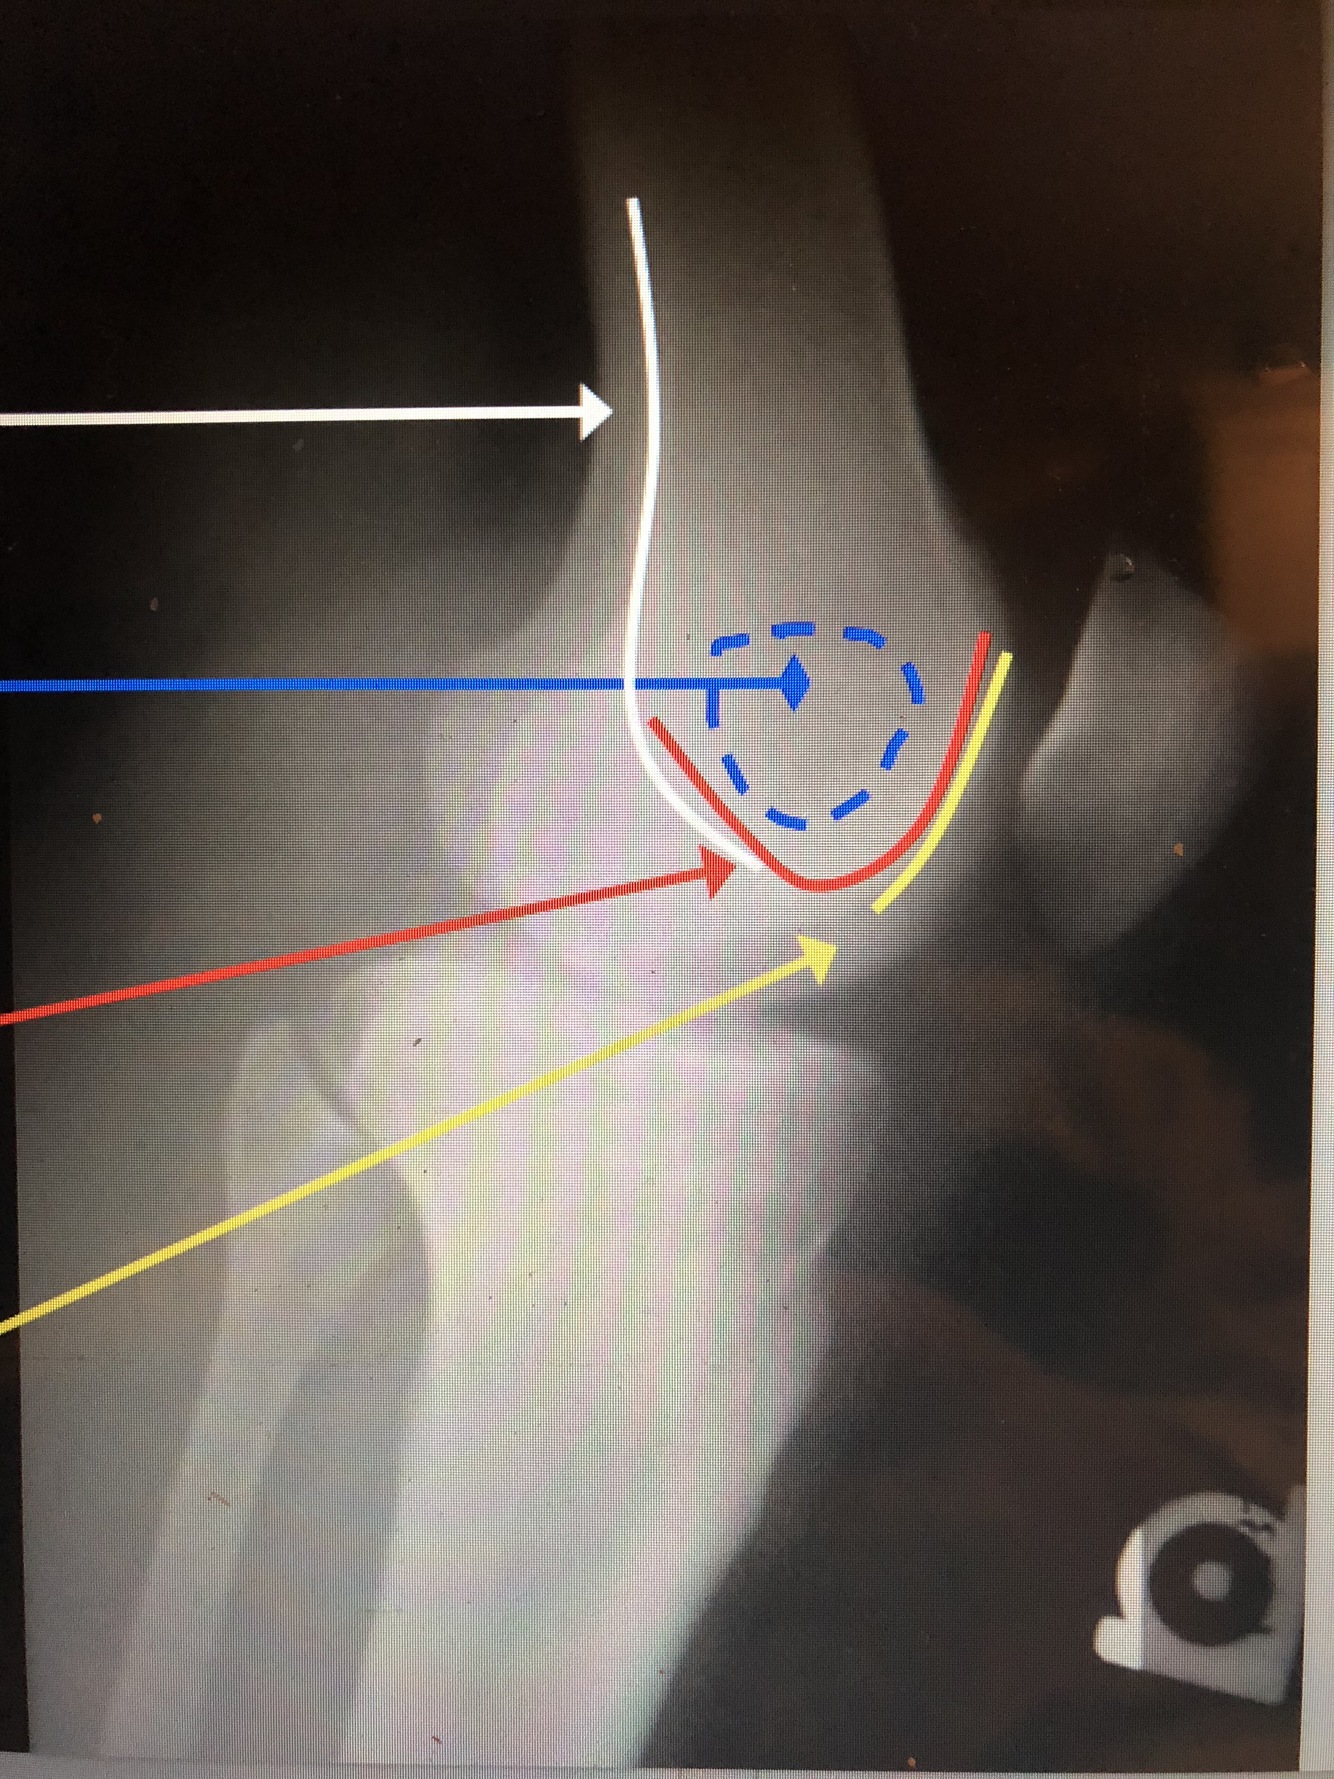

17

Q

What is the blue dotted lines?

A

Ludloff’s Spot – area of lucency in condyles

How well did you know this?

1

Not at all

2

3

4

5

Perfectly

18

What is the red line?

Intercondylar Notch/Groove

19

What is the yellow line?

Patellar Surface of the Femur